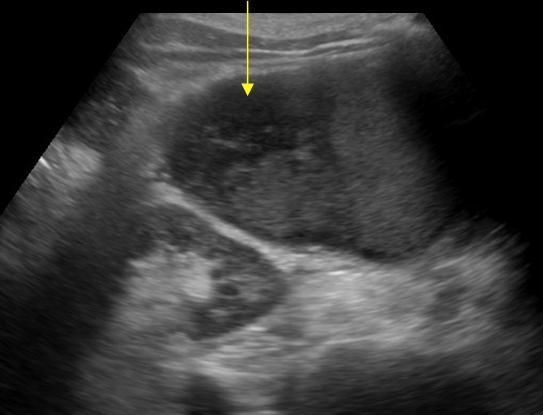

Nhồi máu lách

» Thông tin: Nam giới – 74 tuổi.

» Lâm sàng: Đau mạn sườn trái.